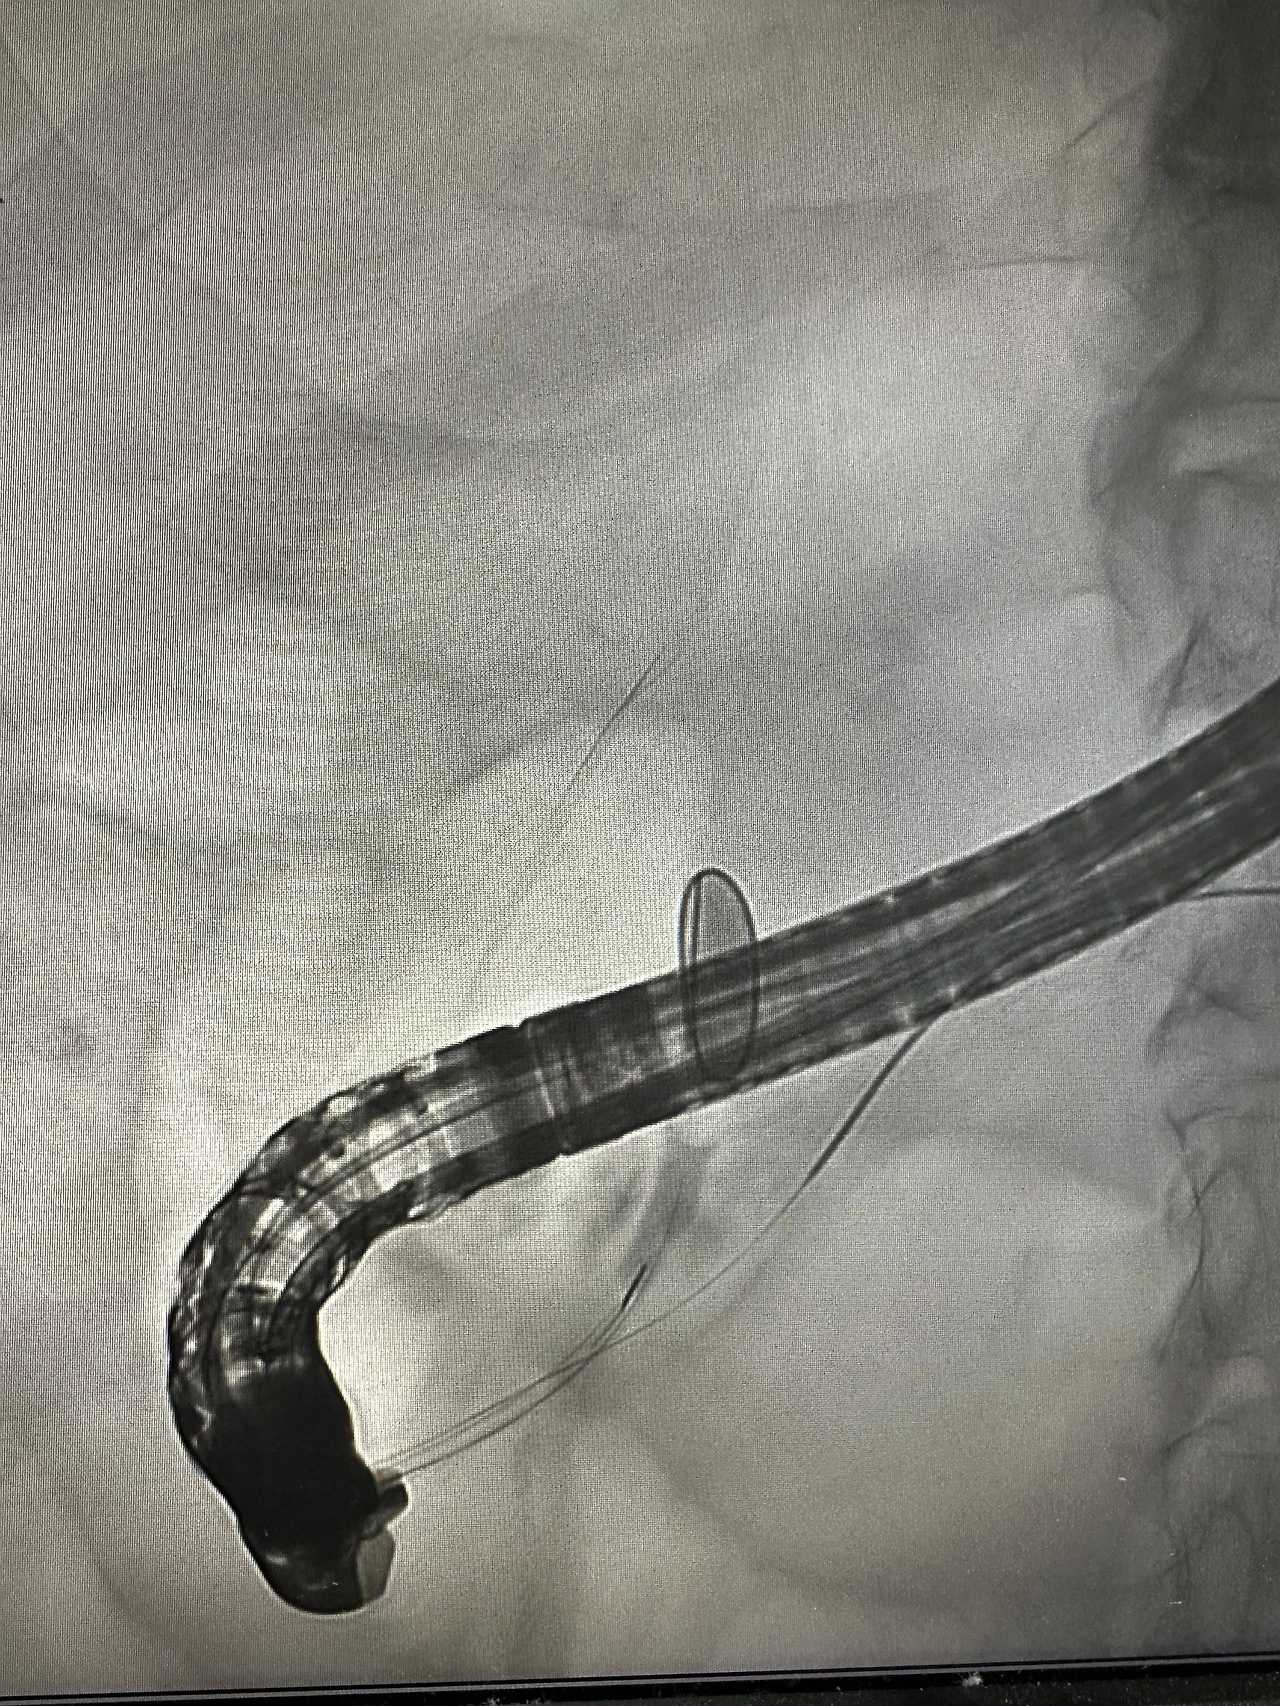

ercp를 하면 재밌는 케이스를 할 때가 있다. 지금은 재밌다고 이야기할 수 있지만, 당시엔 심각하게 접근하고 어렵게 생각할 경우가 많았다. 해결이 되고 결과가 나와서 망정이지 어떻게 해야 하나 싶은 경우도 있다.

bile duct stricture인 이분은 아무리 케뉼레이션을 하고 가이드를 넣으려 해도 들어가지 않았다. 조영제를 넣어도 담관은 보이지 않았다. 과거에 담낭절제술을 했다는 것을 알고 있었지만 클립이 보이거나 수술 흔적은 보이지 않았다. 시절이 시절이니 만큼 실로 봉합부위를 손수 꿰맨 건 아니었을까 하고 교수님과 이야기도 해보았다. 만약 총담관이 막힌 채로 수술이 끝났다면 이분은 살아서 볼 수도 없었을 테니까.

duodenal fistula가 있어서 어딘가로 나오는 게 아닐까? 아니면 수술을 하면서 어딘가에 통로를 만들어 놓은 걸까? 환자의 과거력엔 담낭절제술만 적혀 있었다. 보호자가 뒤늦게 오고 나서야 그 이유를 어렴풋이 짐작할 수 있었다.